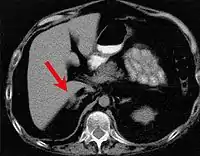

Синдро́м Ка́рнея (ко́мплекс Ка́рни, синдром Карни) — редкое наследственное заболевание с аутосомно-доминантным типом наследования. Характеризуется образованием у детей множественных опухолей (миксомы сердца, пигментные опухоли кожи, пигментная узловая гиперплазия надпочечников, фиброаденомы молочных желез, опухоли яичек, СТГ-секретирующие аденомы гипофиза)[1][2][3]. Следует отличать от триады Карни[4].

Симптомы зависят от размера, подвижности и расположения опухоли. Пятнистая пигментация кожи чаще всего встречается на лице, особенно на губах, веках, конъюнктиве и слизистой оболочке полости рта[2]. Миксома сердца может привести к тромбоэмболии, сердечной недостаточности[6] и может проявляться лихорадкой, болью в суставах, одышкой, диастолическим шумом. Миксома может развиться вне сердца, как правило, на коже и в груди. Клинически эндокринные опухоли могут проявляться в виде расстройств, характерных для синдрома Кушинга.